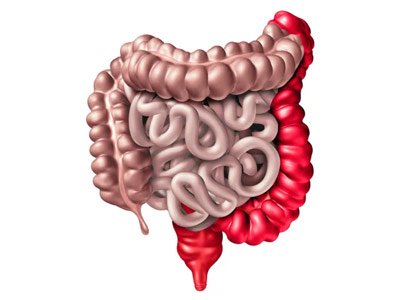

A inflamação do intestino e de doenças que atingem o reto são muito comuns, e as consequências e sintomas são desconfortáveis.

Um intestino inflamado apresenta sintomas como dor abdominal, perda de apetite, emagrecimento, diarreia e sangramentos. Quando esses sintomas estão presentes pensamos em doença de Crohn e retocolite ulcerativa.

Doença de Crohn

Retocolite ulcerativa